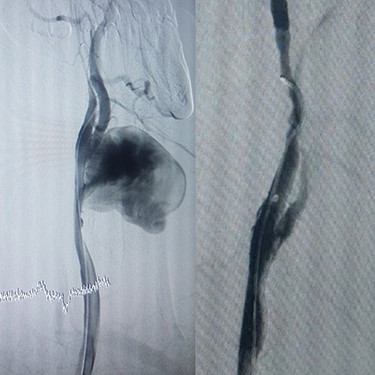

Case 2 — A 32-year-old man with known BD for years, presented to the emergency department with chest pain. We identified left subclavian and thoracic aorta saccular aneurysms on CTA (Fig. 2). Endoxan (1 gr) and Methyl prednisolon pulse (1 gr daily up to 3 days) were injected. The patient underwent a subclavian stent-graft (Fig. 3A) and elective TEVAR (Fig. 3B). Immediate follow-up angiogram revealed the luminal aperture was obtained and it was observed that the pseudoaneurysm remained occluded without a sign of leakage or endoleak. Tablet of prednisolon (5 mg) was prescribed twice daily.

(A) Angiography after stent-graft placement of left subclavian (right), (B) thoracic aorta (left).